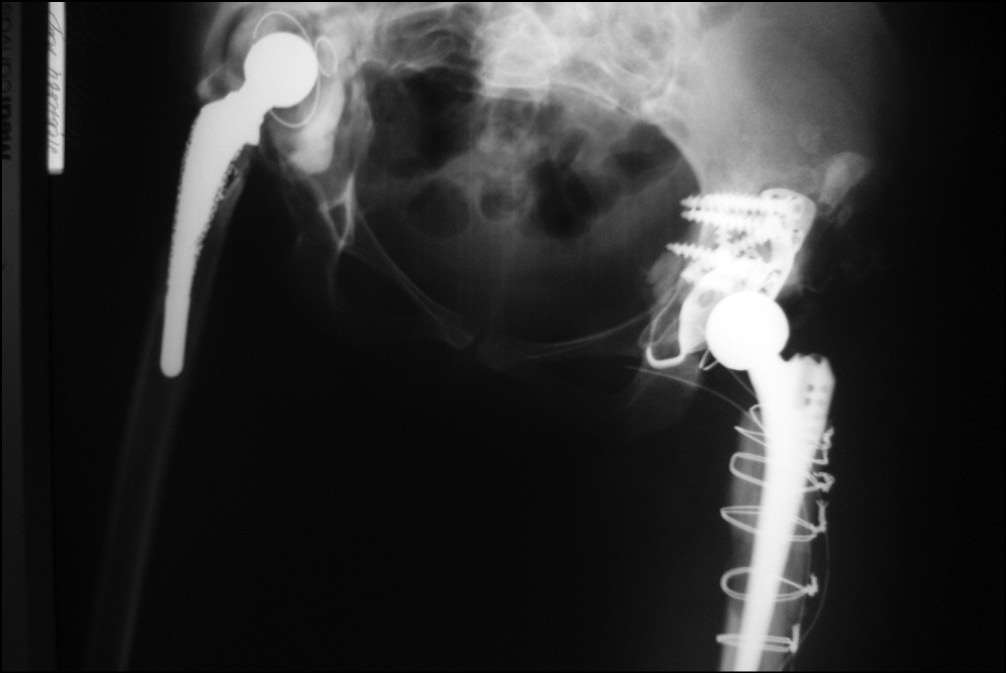

Операцию выполняли в положении больной лежа на здоровом боку с использованием прямого бокового доступа. Удалили рубцово-измененные ткани. При удалении бедренного компонента произошел перелом бедренной кости. Вертлужный компонент с остатками костного цемента удалили без технических трудностей. Выполнили анатомическую установку индивидуальной 3D-конструкции согласно предоперационному планированию и фиксацию 7 винтами.

В полусферическую часть 3D-имплантата установили ацетабулярный компонент цементной фиксации двойной мобильности Novae Stick 45 мм. Проксимальный фрагмент бедренной кости, сломанный при удалении бедренного компонента, фиксировали 5 серкляжными швами и в бедренную кость имплантировали ревизионный бедренный компонент Wagner SL 190/14 (рис. 14).

Рис. 14. Рентгенограмма после операции: достигнута прочная первичная фиксация имплантата в кости, восстановлено анатомическое положение вертлужной впадины

Длительность операции составила 190 мин, кровопотеря — 1500 мл. Продолжительность нахождения пациентки в отделении реанимации — 1 сут. Общая продолжительность стационарного лечения — 14 дней. Послеоперационная рана зажила первичным натяжением. Септических осложнений, вывихов и миграции имплантатов в раннем послеоперационном периоде не было.